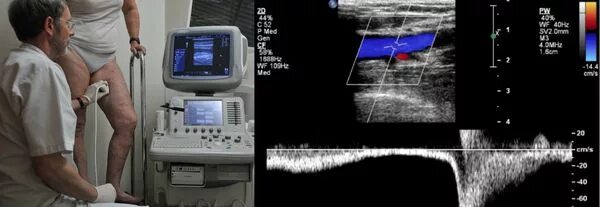

Ангиосканирование нижних конечностей